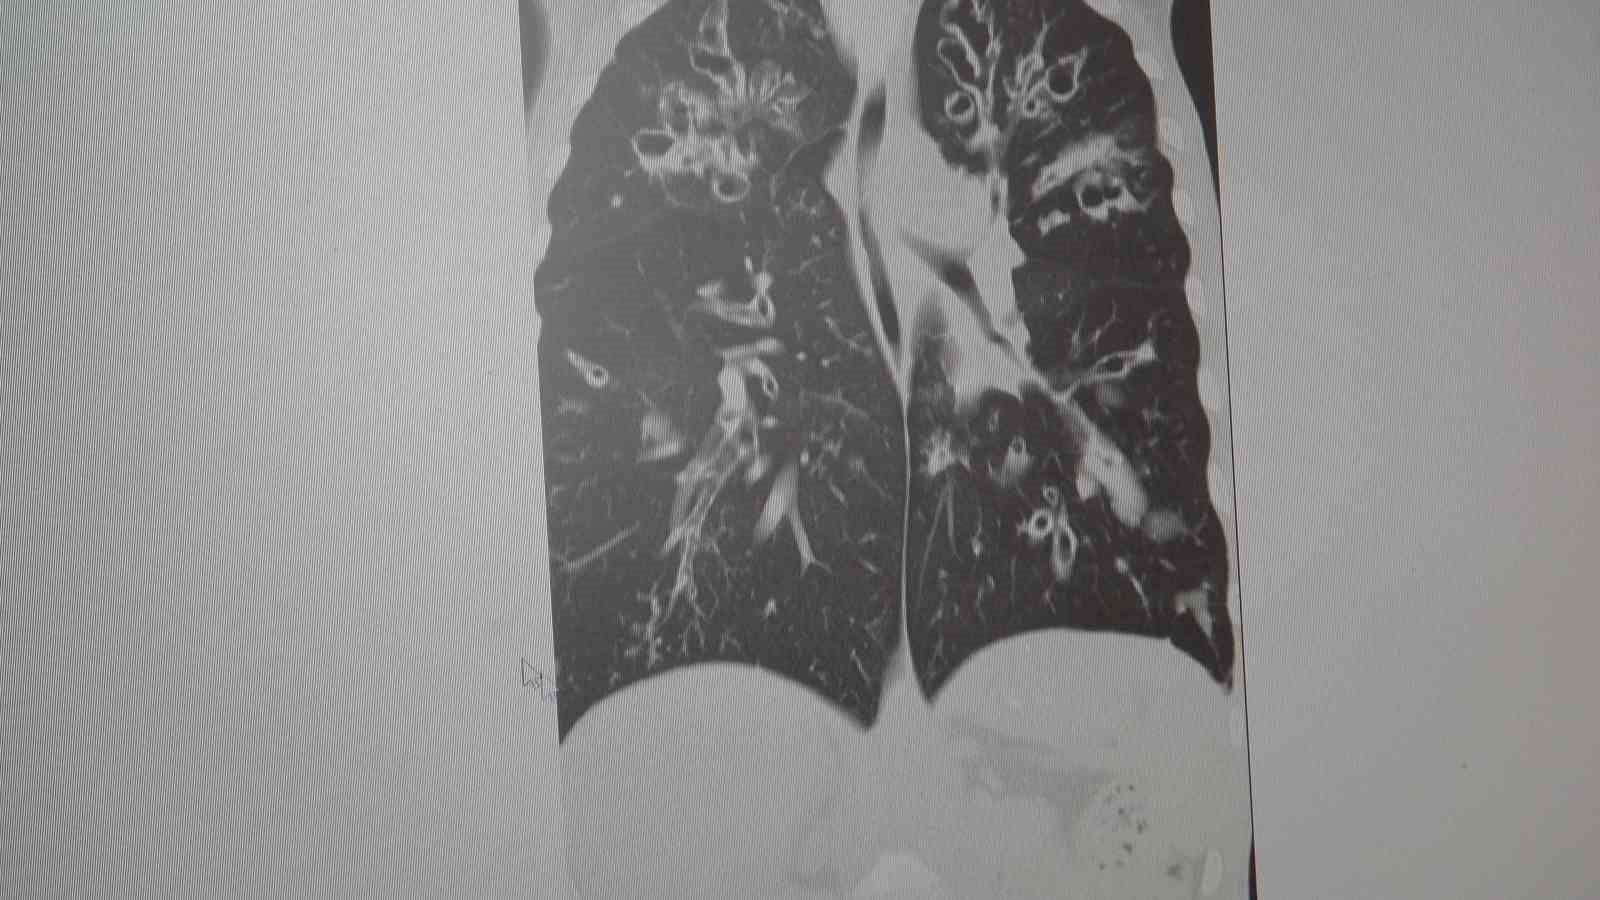

Marmara Üniversitesi Pendik Eğitim ve Araştırma Hastanesi Göğüs Hastalıkları Kliniği’nden Prof. Dr. Sait Karakurt, toplumda sık görülen Kronik Obstrüktif Akciğer Hastalığı (KOAH) ve zatürre hakkında önemli uyarılarda bulundu. KOAH’ın ölümcül hastalıklar listesinde üst sırada yer alan ve toplumda sık görülen bir rahatsızlık olduğunu dile getiren Karakurt, "Vakaların yaklaşık yüzde 85’i sigara kullanımına bağlı" dedi.

Marmara Üniversitesi Pendik Eğitim ve Araştırma Hastanesi uzmanlarından Prof. Dr. Sait Karakurt, dünya genelinde can kayıplarına neden olan hastalıklar arasında 4’üncü sırada yer alan KOAH ve beraberinde getirdiği zatürre riskine karşı önemli açıklamalarda bulundu. Vakaların yüzde 85’inin sigara kullanımı kaynaklı olduğunu vurgulayan Karakurt, KOAH’ın önlenebilir bir hastalık olduğunun altını çizerken; özellikle 65 yaş üstü ve risk grubundaki bireylerin zatürreye karşı aşılama ve erken teşhis konusunda hassas olmaları gerektiğini belirtti.

"KOAH toplumda sık görülen bir hastalıktır ve yaklaşık toplumda bunu yüzde 10 civarında görüyoruz. KOAH, zararlı maddelerin akciğeri parçalamasıyla oluşan bir rahatsızlık ve bunun da en önemli nedeni sigara. Vakaların aşağı yukarı yüzde 85’i sigara kullanımından kaynaklıdır. Bunun dışında hava kirliliği, iş yerlerinde kimyasal maddelere maruz kalma ve enfeksiyonlar da yine KOAH’ın nedenleri arasındadır. KOAH’ın önemi şu; bugün Dünya Sağlık Örgütü’nün (DSÖ) dünyada insanları öldüren hastalıklar listesinde ilk 10’da 4’üncü sırada yer alıyor. KOAH önlenebilir bir rahatsızlıktır; sigaranın bırakılmasıyla birlikte tamamen ortadan kalkacaktır."

KOAH’ın akciğer dokusunu tahrip eden bir hastalık olduğunu ve bu nedenle de hastaların enfeksiyona açık hale geldiğine dikkat çeken Karakurt, "Akciğer dokusunun tahrip olduğu her durumda hastaların enfeksiyona karşı eğilimi artar ve enfeksiyona yakalandıkları zaman bunun geçmesi güç olur. KOAH’lı hastalar zatürre geçirdikleri zaman öksürük ve balgam artışı gibi bir takım belirtiler gelişir. Ayrıca ateşin 38,5 derecenin üstüne çıkması, nefes darlığının artması, titremeyle birlikte ateşin yükselmesi ve bir takım bilinç bozukluğu gibi belirtiler hastanın zatürre olduğunu gösterebilir. Bu nedenle hastaların erkenden doktora başvurmaları önemlidir" şeklinde konuştu.